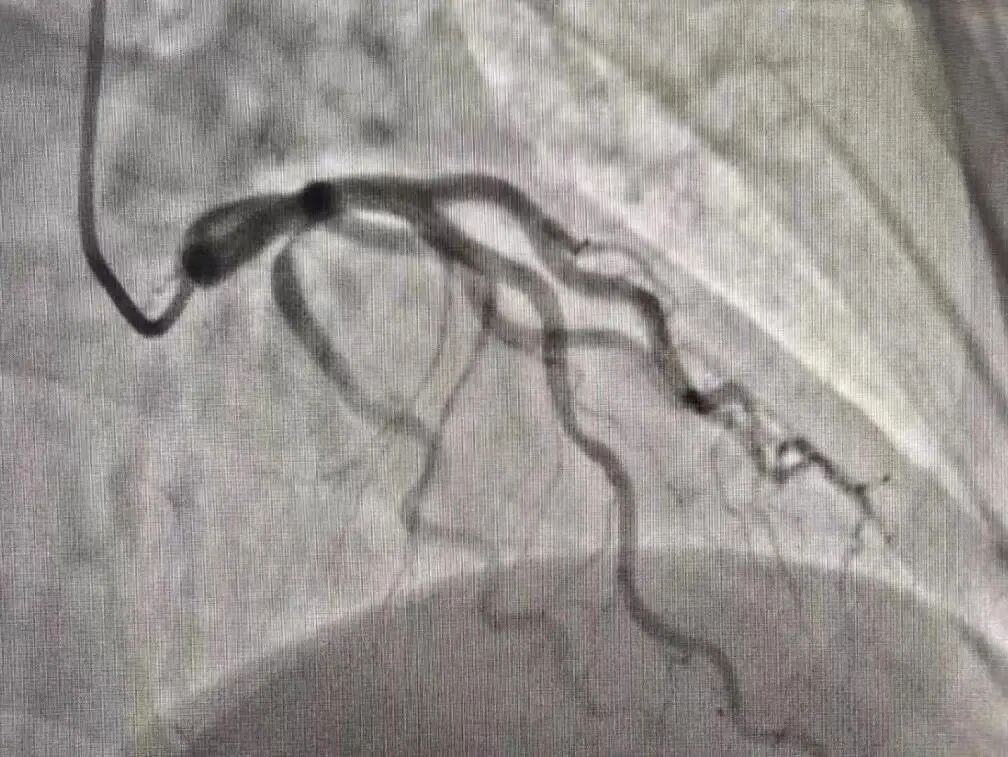

胸部血管系统

DSA 技术可用于心脏以及周围大血管的成像,其主动脉弓以及主动脉显示上更加的清晰。可用于诊断主动脉夹层动脉瘤及显示大动脉炎病变范围。